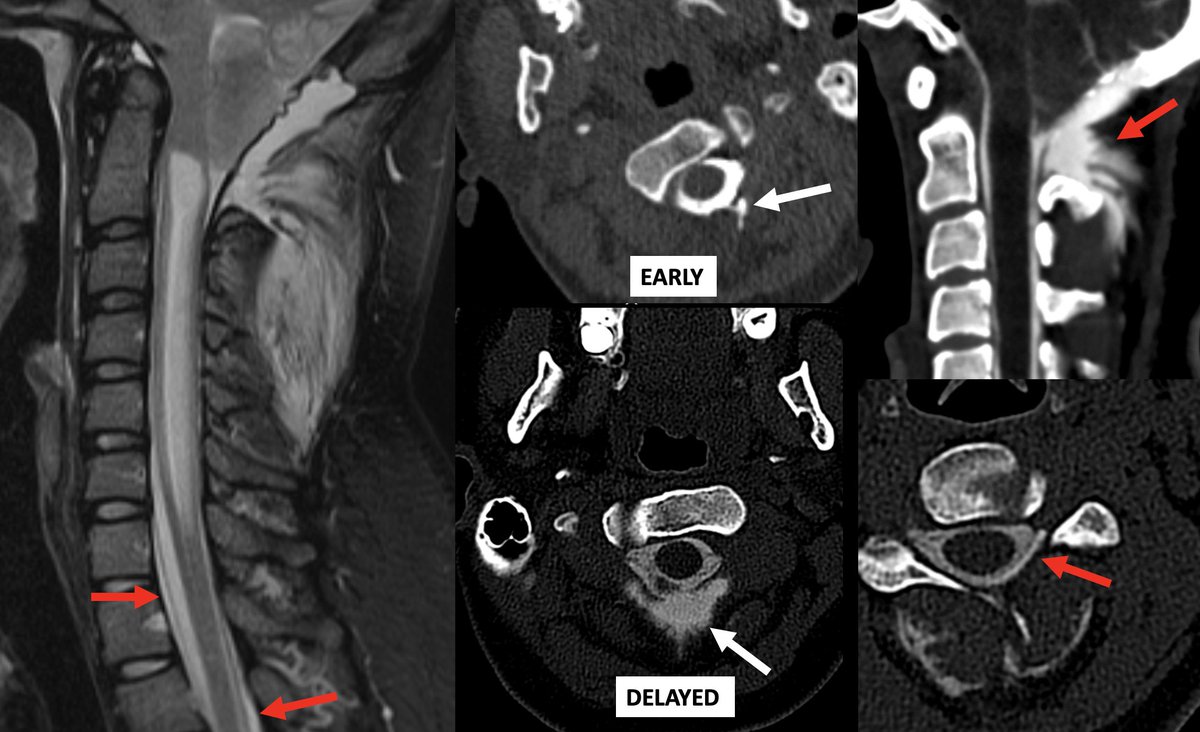

We know the false localizing sign in #SIH posterior to C2 due to anatomic communication of the epidural space and posterior spinal soft tissues. This patient has a "reverse" false localizing sign, presenting after suboccipital crani with leaking duraplasty into epidural space!